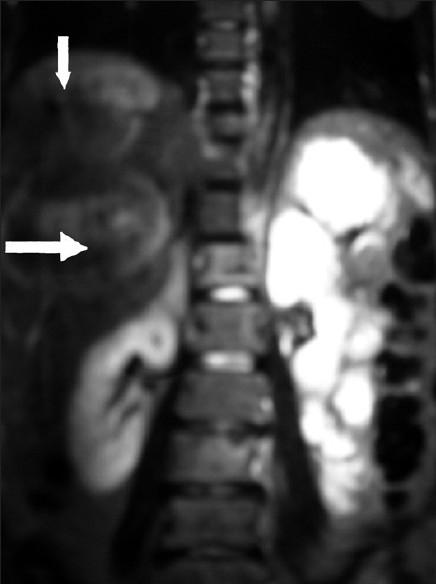

一名绝经前女性患有多器官转移的子宫内膜样腺癌。

Endometrioid endometrial adenocarcinoma in a premenopausal woman with multiple organ metastases.

Endometrial adenocarcinoma is the third common malignancy of the female genital tract occurring most often in the postmenopausal age group. High tumor grade, advanced surgical stage, and lymphovascular space invasion are implicated as poor prognostic factors for dissemination of disease. We present an unusual case of endometrial adenocarcinoma in a premenopausal woman with simultaneous metastases in brain, liver, skin and skeletal system, within one month of completion of treatment. The role of adjuvant/concurrent chemotherapy in addition to radiotherapy in high risk cases is discussed along with the review of literature.

子宫内膜腺癌是女性生殖道第三常见的恶性肿瘤,最常发生于绝经后年龄组。高肿瘤分级、手术分期晚以及淋巴管间隙浸润被认为是疾病播散的不良预后因素。我们报告了一例绝经前女性子宫内膜腺癌的罕见病例,在完成治疗后的一个月内,脑、肝、皮肤和骨骼系统同时出现转移。本文结合文献复习,讨论了高危病例中辅助/同步化疗联合放疗的作用。